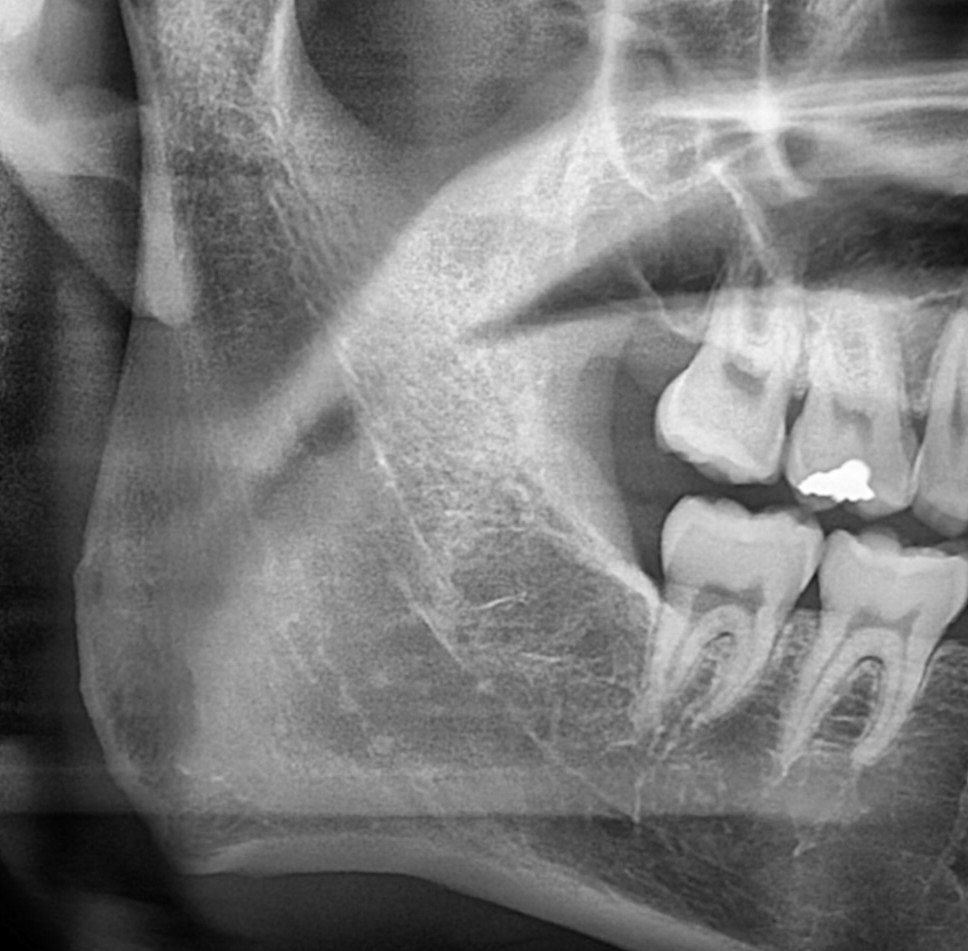

안녕하세요 제가 왼쪽 아래에 큰 사랑니가 있는데요, 맨 끝 어금니 뿌리와 닿아있어 계속 놔두면 뿌리 흡수가 염려되는 상황입니다..그런데 인터넷 검색하다보니 어금니를 발치하는 상황이 올 경우 교정혹은 이식해서 사랑니로 그 자리를 대신하는 경우가 있더라고요, 제 경우도 그렇게 대신할 수 있는건지 여쭤보고 싶습니다..만약에 안 된다면 오른쪽이나 왼쪽 어금니 다른 부위는 그렇게 대신하는게 가능한지 여쭤봅니다..

• 2번 째 사진

사진으로 보이는 부위는 오른쪽 부위이기 때문에 정확한 치아의 관계를 판단하기 힘드나 어금니를 발치하고 사랑니를 어금니 처럼 사용하기 위해서는 교정치료가 필요할수 있습니다.

1. 올리신 방사선 사진은 말씀하신 왼쪽 부위가 아닌, 오른쪽 부위에 해당하는 방사선 사진입니다.(사람의 정면 사진은 바라보고 있다고 생각하시고 방향을 생각해보시면 좌우가 반대입니다)

현재 올려주신 사진으로는 알 수 없습니다. 오른쪽 사진을 올려주셨는데, 여기엔 사랑니가 없습니다.

사랑니가 매복되고 기울어져있는경우, 그 앞의 치아의 뿌리를 흡수시키거나, 충치를 유발하는 경우는 있습니다.

하지만, 앞의 어금니를 빼고 그자리를 사랑니로 대체하기 위해서는, 사랑니가 기울어지지않고 정상적으로 맹출되었을 경우에 가능합니다.